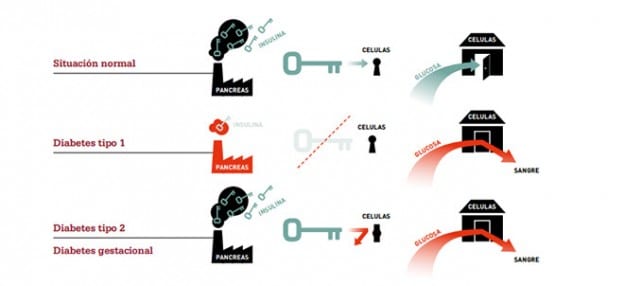

En primer lugar, hay que saber que hay varios tipos de diabetes mellitus, que es una enfermedad autoinmune que afecta